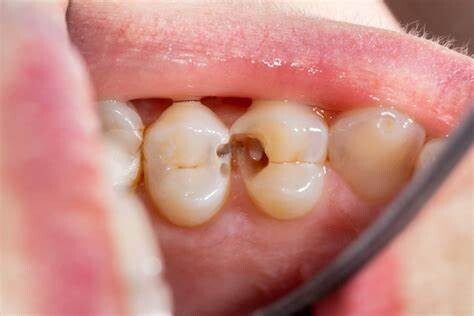

A dental cavity forms when plaque, a sticky bacterial film that builds up inside the mouth, solidifies and creates an area of decay. This bacteria combines with sugar to produce acids that dissolve the tooth's enamel, the hard surface that works as a protective layer against tooth decay. And when this protective layer begins to wear, different types of cavities have the potential to form.

Have you ever wondered what areas of the mouth are most prone to tooth decay? Well, not all teeth are created equal. Plaque tends to accumulate more easily in certain areas. For example, the back teeth' pits and fissures (molars) are a hot spot for plaque and the spaces in between the teeth. Plaque also builds up easily along the gumline, and when this plaque isn't removed, a gumline cavity can form.